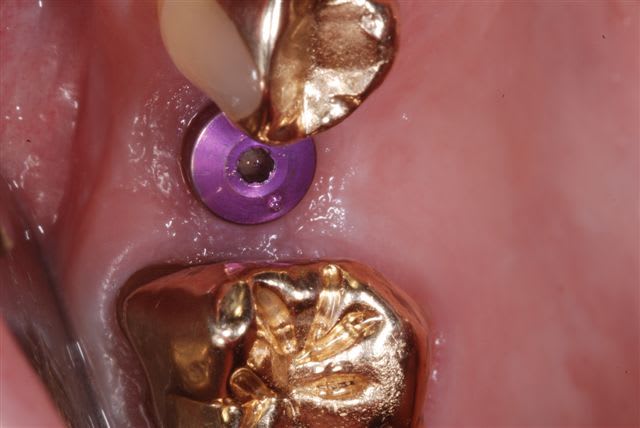

comparaison photos prises avec flash Metz 15 et sigma 140 DG, même boitier (Nikon D80) iso 100, f32, i-ttl, mise au point manuelle.

bon alors pour faire comme suggéré par D57:

(f16, iso 100, même cadrage, boitier et rapport d'agrandissement, i-ttl)

voilà typiquement la différence obtenue entre ces deux flashs